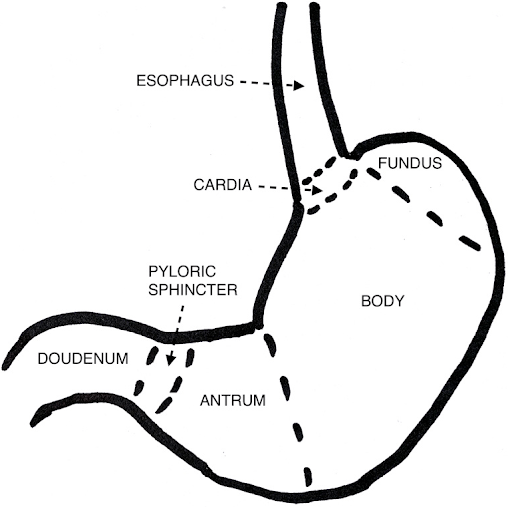

Flynn et al. conducted a narrative review of the anatomy of the stomach and adjacent organs, exploring how ultrasound can be utilized to assess gastric content and predict the risk of pulmonary aspiration of gastric contents.